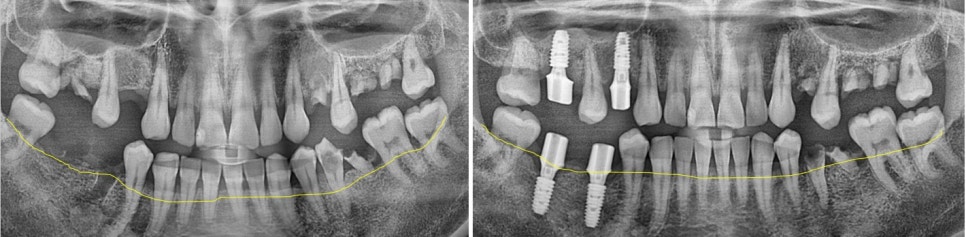

▲ 뼈이식 전 ▲ 뼈이식 후

차이가 보이실까요?

이렇게 잇몸뼈가 제대로 차오를 때까지 환자분께서는 3개월 정도 걸리셨습니다.

오른쪽 편 사진은 잇몸뼈가 만들어진 후 위에 최종 보철을 올리기 전에 중간에 커스텀 힐링을 장착한 모습입니다.

▲치료 완료 후 파노라마 사진

이렇게 다른 구치부 치아들은 신경치료와 크라운 치료, 레진 치료

노란 박스로 표시된 치아들은 모두 임플란트 치료로 도와드렸습니다.

이렇게 치료 최종 치료 기간까지는 23. 8월~24. 7월에 마무리하셔서 거의 1년 정도 소요가 되었습니다.